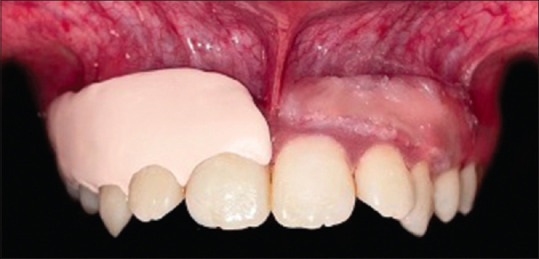

Abstract Image